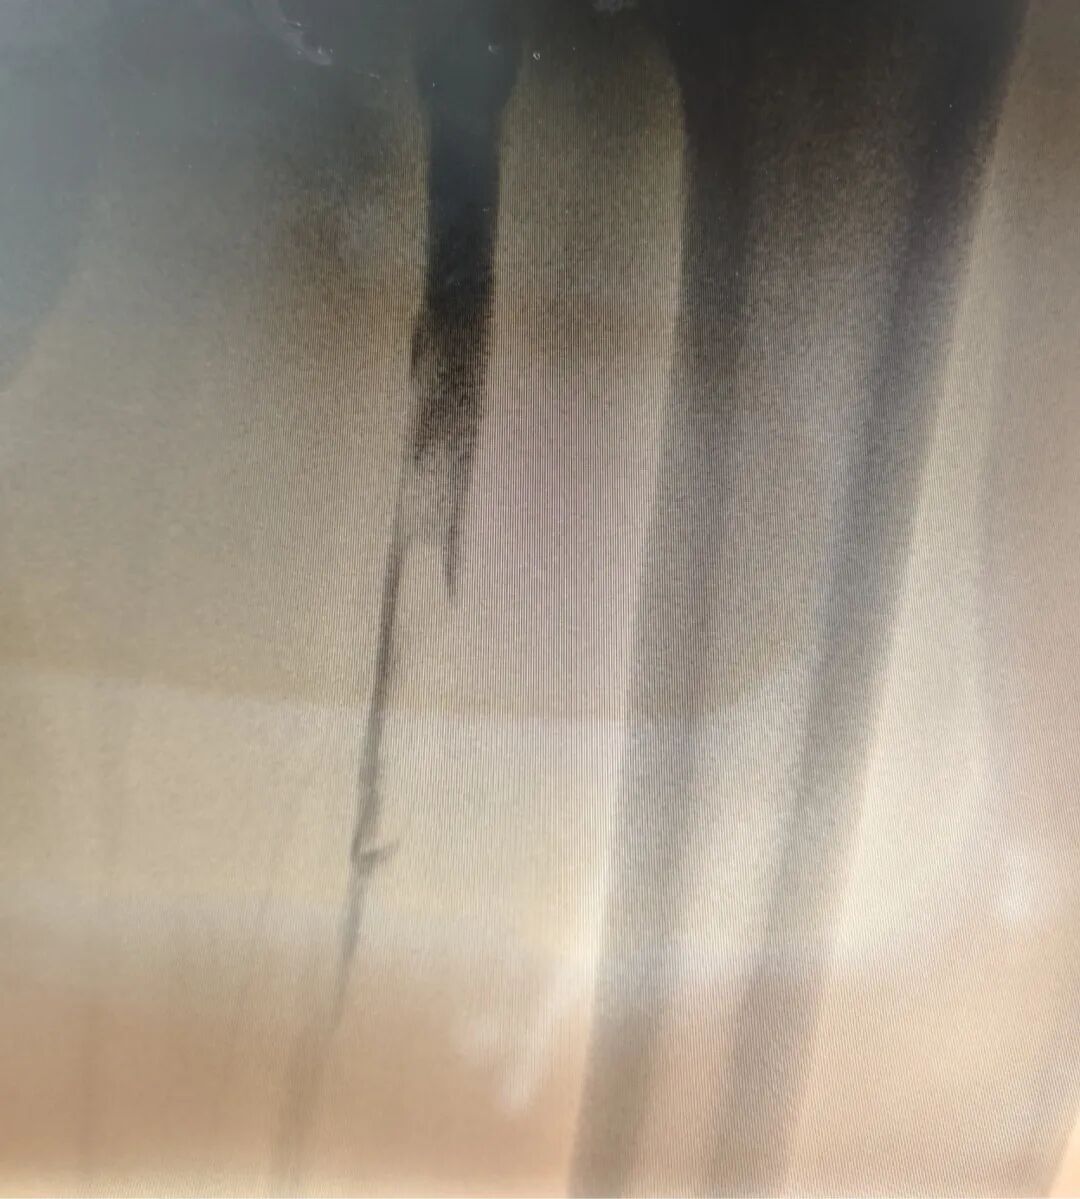

术中造影

田明主任精准操作,经鞘管将静脉取栓支架推送至髂总静脉,并一路延伸至股浅静脉,通过四次小心翼翼的反复拉栓,成功清除大量血栓。最终,复查造影传来捷报:患者股浅静脉、髂静脉及股静脉血流通畅,未见残余血栓,手术获得圆满成功!这一结果让手术室里的所有人都松了一口气,也意味着这场与病魔的激烈较量取得了阶段性的胜利。